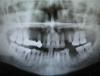

kasatka Опубликовано 5 июня, 2009 Автор Поделиться Опубликовано 5 июня, 2009 (изменено) Вот,съездила в клинику,взяла.Правда- когда вывешиваю здесь- полосы. Ну эту кисту хорошо видно. Изменено 5 июня, 2009 пользователем kasatka Ссылка на комментарий

kasatka Опубликовано 5 июня, 2009 Автор Поделиться Опубликовано 5 июня, 2009 и вот еще Ссылка на комментарий

Sahan Опубликовано 5 июня, 2009 Поделиться Опубликовано 5 июня, 2009 и вот ещеСпасать здесь нечего. Удалять зуб, ревизия лунки и имплантация немедленная или через 6 недель плюс костная пластика. Ссылка на комментарий